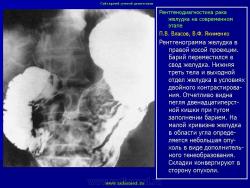

"Лучевая семиотика" рака желудка

Мы предлагаем определенный симптомокомплекс, характеризующий начальные проявления рака желудка, названного нами внутристеночным бластоматозным инфильтратом. Его основные признаки: неровность контура желудка на протяжении 1-3 см и, соответственно, на этом уровне утолщение стенки за счет ее опухолевой инфильтрации.

Сегодня следует говорить о двух основных рентгенологических симптомах рака желудка: неровность его контура в фазу плотного наполнения бариевой взвесью и утолщение стенки желудка, выявляемое с помощью двойного контрастирования. Оба этих симптома имеют весьма многогранную палитру своего отображения: от буквально мизерных признаков неровности контура желудка и очень незначительной (до 3-4 см) по протяженности и степени утолщения стенки при двойном контрастировании.

Характерными лучевыми признаками "малого" рака являются неровность контура желудка на небольшом протяжении (1-3 см), выявляемое при плотном наполнении и соответственно этому участку утолщение стенки при двойном контрастировании. Ригидность стенки желудка, свойственная распространенным формам рака желудка, обычно определяется лишь при размерах опухоли от 3-4 см и более и часто сочетается с изъязвлением.

Двойное контрастирование имеет преимущество главным образом при выявлении "малого" рака тела и верхнего отдела желудка. Однако в ряде случаев оно позволяет детализировать характер изменений и в его дистальном отделе, особенно при наличии опухолевой инфильтрации, приводящей к утолщению стенки, что особенно характерно для эндофитного рака.